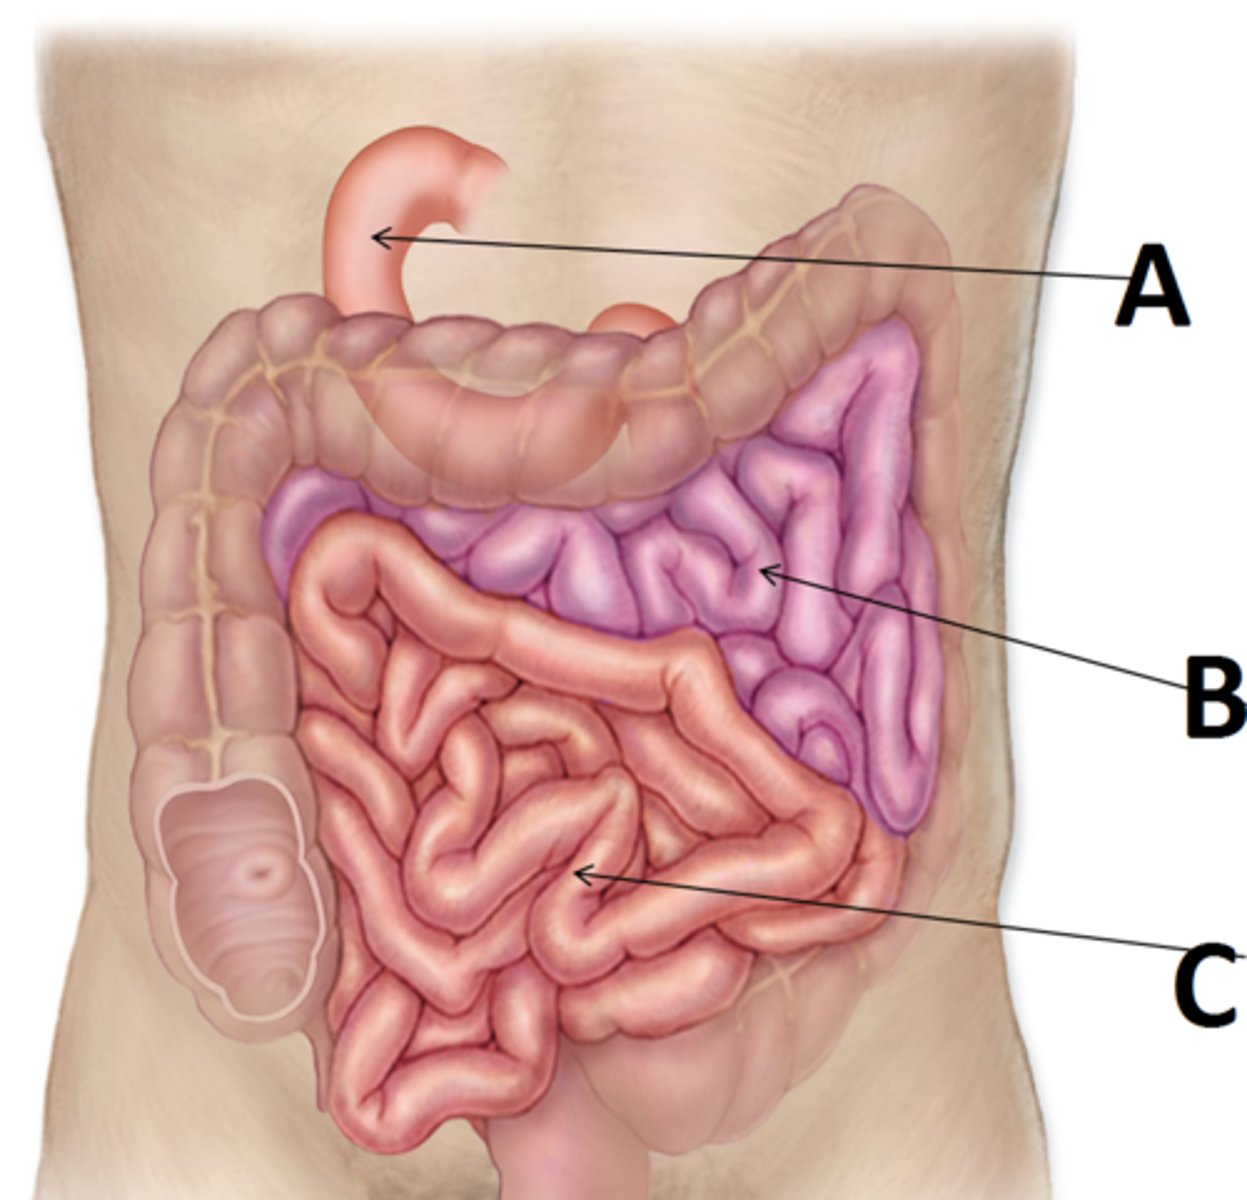

small intestine

duodenum

A

jejunum

B

ileum

C